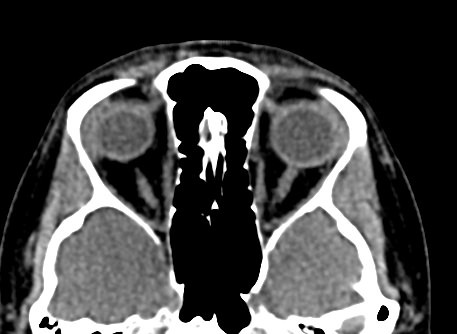

Орбиты (или глазницы) – это костные углубления в лицевом черепе, где расположены глазные яблоки, окруженные жировой клетчаткой, а также слезные железы, слезные каналы, сосуды, нервы, мышцы и связки глаза. Такая небольшая по объему область содержит важные анатомические структуры, обеспечивающие нормальную функцию органа зрения.

Кроме того, область орбиты тесно связана с близлежащими структурами – полостью черепа с расположенным в ней головным мозгом, а также с полостью носа, околоносовыми пазухами и носоглоткой. Различные патологические процессы могут развиваться как в самой глазнице, так и в околоорбитальных структурах, но при этом распространяться на область орбит.

Сложное строение глазницы и взаимосвязь с соседними анатомическими структурами затрудняет диагностику заболеваний глазного яблока и его придатков. Одним из наиболее информативных методов обследования органа зрения и окружающих тканей является мультиспиральная компьютерная томография. Кроме высокой информативности методика отличается быстротой и неинвазивностью (то есть не требует вмешательства в организм человека). Принцип получения изображений построен на применении ионизирующего излучения и разной способности тканей поглощать рентгеновские лучи.

Мультиспиральная компьютерная томография лучше всего визуализирует ткани с высокой плотностью, к которым, в частности, относится костная ткань. Это делает КТ незаменимой при диагностике травматических повреждений глазниц, а также для выявления инородных тел орбит.

По результатам КТ орбиты глаза врач может оценить состояние:

- костных стенок глазницы, верхней и нижней глазничных щелей;

- глазных яблок

- стекловидного тела;

- мышц глаза: нижней, верхней, косой, прямых мышц (латеральной и медиальной);

- глазничной артерии и вены;

- зрительных нервов;

- слезных желез;

- ретробульбарной (расположенной позади глазного яблока) клетчатки.